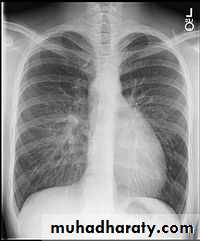

CXR of adult male PA and lateral views, it shows :Normal both lung fields ,Central cardiac shadow, Central trachea, central mediastinum, No boney lesions, no soft tissue abnormalitiesnormal radiologic anatomy of the chest Look carefully on both diaphragmatic cruse costo & cardio phrenic angles. Useful in detection of pleural effusion

10.normal chest anatomy

Upper zone>>>> 1st and 2nd ribsMiddle zone>>>> 3rd and 4th ribsLower zone>>>> 5th and 6th ribsHow to asses cardiac size We take 2 lines the between borders of cardiac shadow and 2 lines between the inner surface of thoracic cage and the ribsCardiothoracic ratio (CTR) =Cardiac Width : Thoracic WidthA CTR of greater than 1:2 (50%) is considered abnormal.